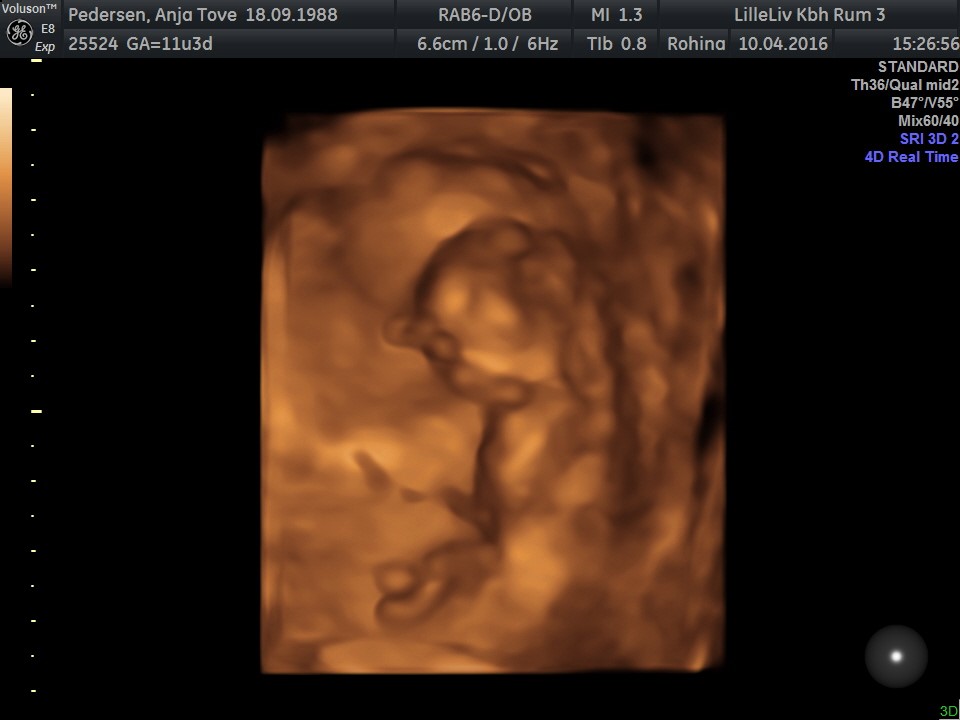

Der var meget lang ventetid så vi fik lige lov til at se i 3D og 4D selvom vi ikke havde betalt for det - så fantastisk en oplevelse!

Hun behøvede slet ikke at lede efter hjertet, for den hoppede lystigt rundt derinde. Og hver gang hun satte 4D til for at se bevægelser så lå den stille, en rigtig bølle

Ansigtet skulle vi så heller ikke se for arme og hænder lå konstant oppe ved hovedet